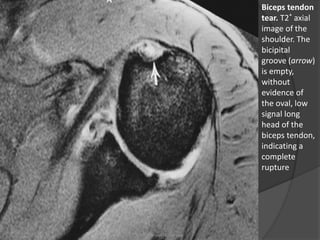

Biceps tendon

tear. T2* axial

image of the

shoulder. The

bicipital

groove (arrow)

is empty,

without

evidence of

the oval, low

signal long

head of the

biceps tendon,

indicating a

complete

rupture

Lacerações, Degeneração e Luxaçãodos Tendões  Cabeça Longa do Bíceps – Lacerações:  Encontra-se associado a lacerações do tendão do supra-espinhal em 7% dos casos.  Geralmente ocorre na zona de compressão imediatamente proximal ao sulco bicipital e em indivíduos mais velhos.  O fragmento distal do tendão e o músculo podem se retrair distalmente, e um sulco bicipital vazio pode ser demonstrado em imagens axiais. Dr. Emanuel R. Dantas

• 37.

Biceps tendon tear. T2*axial image of the shoulder. The bicipital groove (arrow) is empty, without evidence of the oval, low signal long head of the biceps tendon, indicating a complete rupture Dr. Emanuel R. Dantas